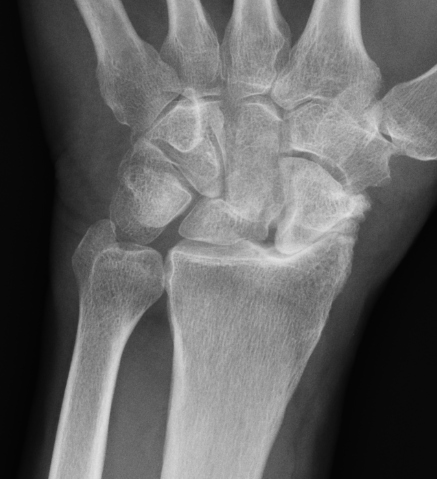

Rheumatoid wrist

SLAC wrist

SNAC wrist

Kienbock's disease